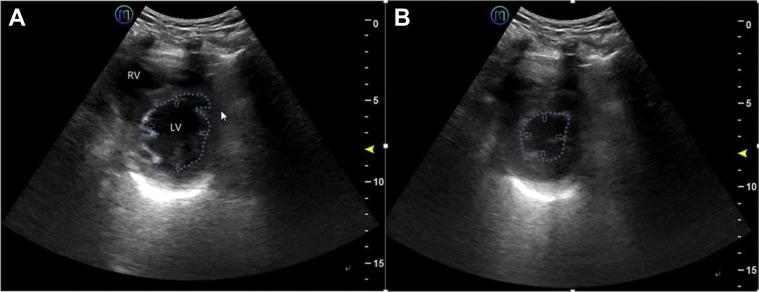

Twenty-three patients with COVID-19 were included and divided into two groups. Twelve were nonsevere cases, and 11 were severe cases. All patients underwent a 5G-based robot-assisted remote ultrasound system examination of the lungs and heart following an established protocol. Distribution characteristics and morphology of the lung and surrounding tissue lesions, left ventricular ejection fraction, ventricular area ratio, pericardial effusion, and examination-related complications were recorded. Bilateral lung lesions were evaluated by using a lung ultrasound score.

The remote ultrasound system successfully and safely performed cardiopulmonary examinations of all patients. Peripheral lung lesions were clearly evaluated. Severe cases of COVID-19 had significantly more diseased regions (median [interquartile range], 6.0 [2.0-11.0] vs 1.0 [0.0-2.8]) and higher lung ultrasound scores (12.0 [4.0-24.0] vs 2.0 [0.0-4.0]) than nonsevere cases of COVID-19 (both, P < .05). One nonsevere case (8.3%; 95% CI, 1.5-35.4) and three severe cases (27.3%; 95% CI, 9.7-56.6) were complicated by pleural effusions. Four severe cases (36.4%; 95% CI, 15.2-64.6) were complicated by pericardial effusions (vs 0% of nonsevere cases, P < .05). No patients had significant examination-related complications.

共纳入 23 例 COVID-19 患者,分为非重症组 12 例和重症组 11 例。所有患者均按既定方案接受基于 5G 的机器人辅助远程超声系统的肺部和心脏检查。记录肺部和周围组织病变的分布特征和形态、左心室射血分数、心室面积比、心包积液和与检查相关的并发症。采用肺部超声评分评估双侧肺部病变。

远程超声系统成功、安全地对所有患者进行了心肺检查。外周肺部病变得到了清晰的评估。COVID-19 重症患者的病变区域明显更多(中位数[四分位间距],6.0[2.0-11.0]比 1.0[0.0-2.8]),肺部超声评分更高(12.0[4.0-24.0]比 2.0[0.0-4.0])(均 P<0.05)。1 例非重症患者(8.3%;95%CI,1.5-35.4)和 3 例重症患者(27.3%;95%CI,9.7-56.6)并发胸腔积液。4 例重症患者(36.4%;95%CI,15.2-64.6)并发心包积液(而非重症患者为 0%,P<0.05)。没有患者出现明显的与检查相关的并发症。